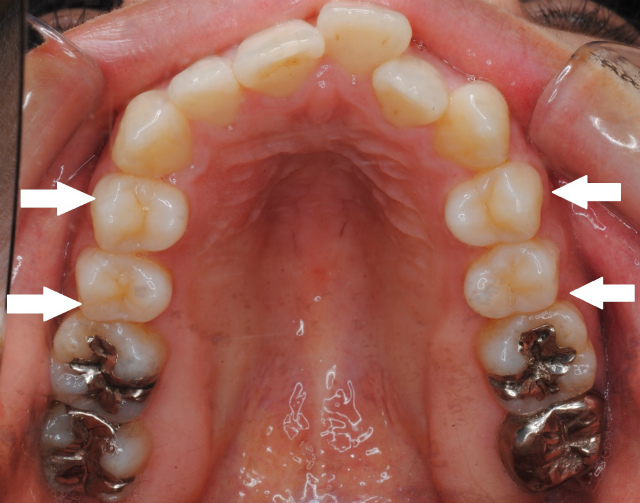

矯正したのに後戻り 舌癖の改善 クローバー歯科 矯正歯科医監修コラム